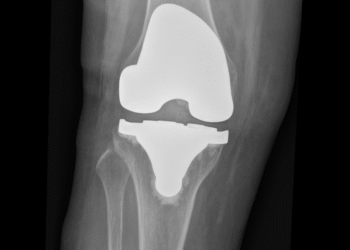

HÌNH ẢNH SAU THAY KHỚP GỐI